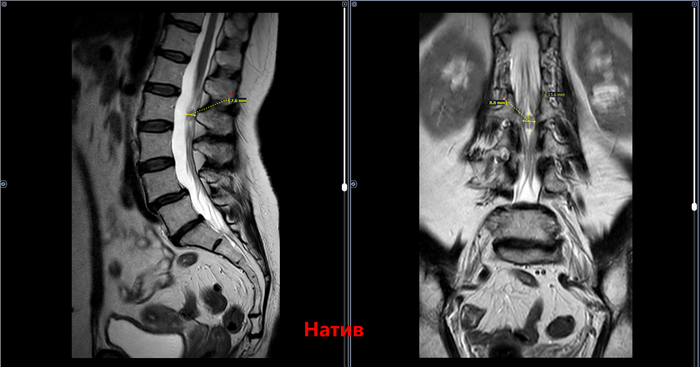

МРТ возрастной пациентки, поясничного отдела позвоночника с контрастным усилением, жалобами на боль в пояснице с иррадиацией в левую нижнюю конечность

Интрадурально на уровне тела L2 позвонка визуализируется патологическое образование, овальной формы, с четкими ровными контурами, неоднородной структуры, характеризующееся преимущественно изогиперинтенсивным МР-сигналом на Т2-ВИ и изо- на Т1-ВИ. После внутривенного введения парамагнитного контрастного вещества отмечается его равномерное накопление образованием, размером до 13х8х7 мм . Других участков патологического накопления не определяется .Определяется смещение тела L4 позвонка кпереди относительно тела L5 позвонка на 3,5 мм. В L4-L5 определяется дорзальная протрузия межпозвонкового диска размером 2.6мм. В L5-S1 определяется дорзальная левосторонняя фораменальная протрузия диска размером 3 мм. Дегенеративно-дистрофические изменения.

МР-картина интрадурального объемного образования на уровне тела L2 позвонка (соответствует невриноме). МР-картина дегенеративно-дистрофических изменений пояснично-крестцового отдела позвоночника. Антесподилолистез L4-L5. Протрузии дисков L4-L5, L5-S1.